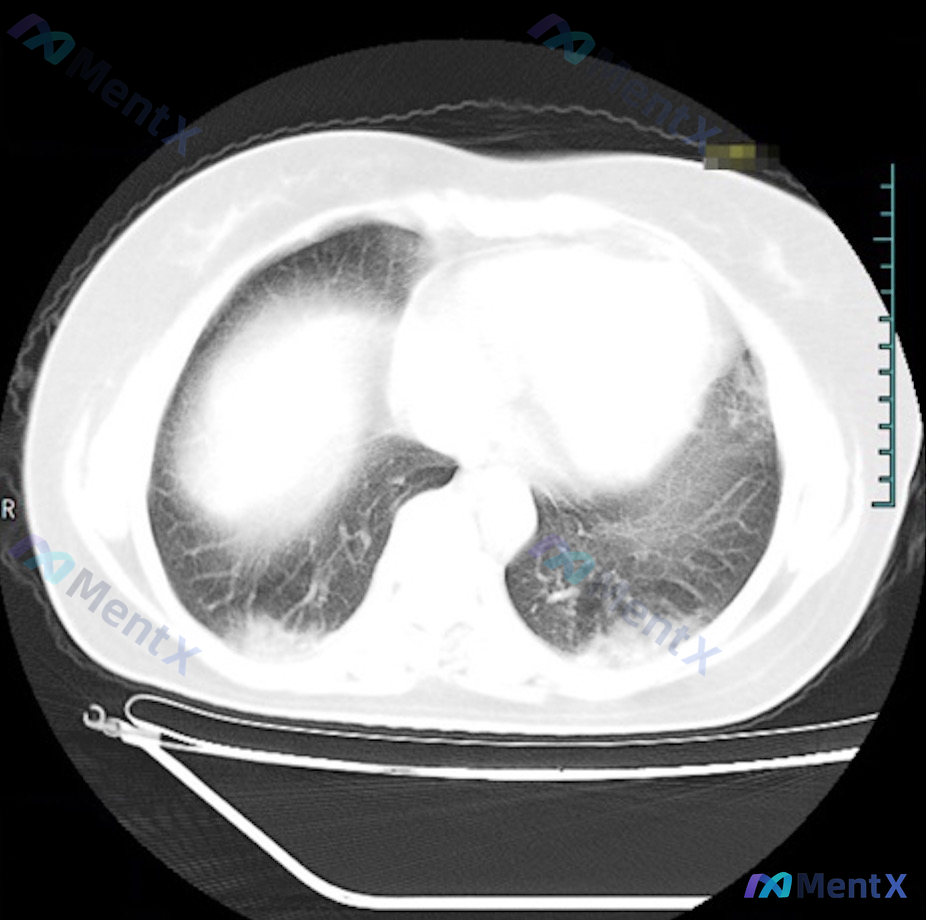

这个双肺底对称性实变磨玻璃影,第一反应会先考虑感染吗?

整理到一份胸部CT肺窗横断面的影像分析资料,先不放临床背景,只看影像特征,大家第一眼的鉴别思路会怎么排? 核心影像表现: - 病灶位置:严格局限于双肺下叶背侧近后胸壁处(坠积部位),双侧对称 - 密度:以实性为主,伴部分磨玻璃样改变 - 边缘:模糊,与正常肺组织界限不清 - 其他:未见明确结节、空洞...